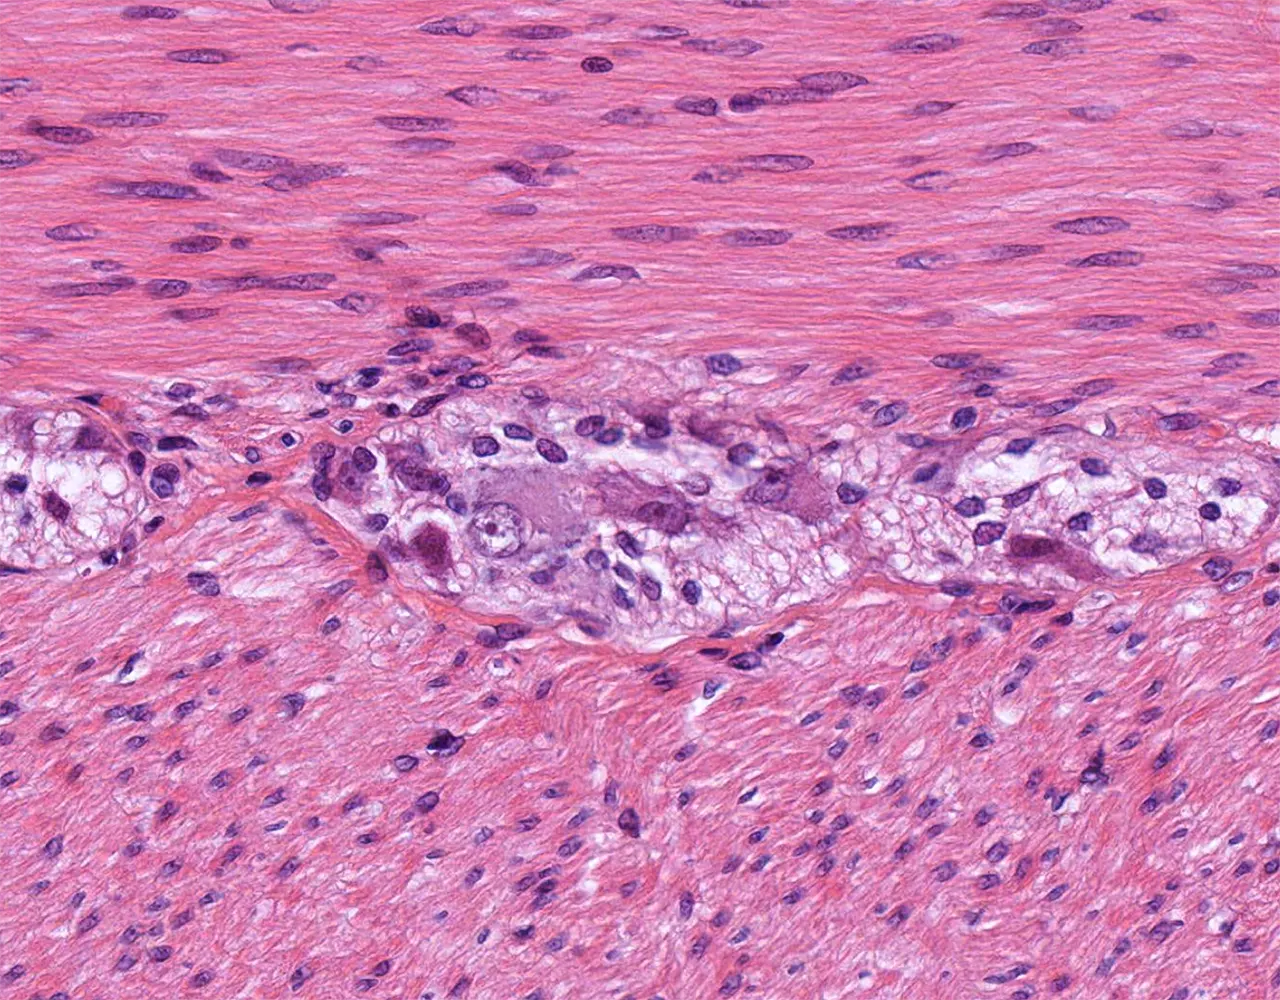

- Le gros intestin comprend le caecum, le côlon, le rectum et le canal anal.

- Le gros intestin est responsable de l’absorption de l’eau et des électrolytes, de la sécrétion de mucus pour la lubrification, de la compaction et du stockage des matières fécales, ainsi que de la contribution aux interactions entre l’hôte et le microbiote.